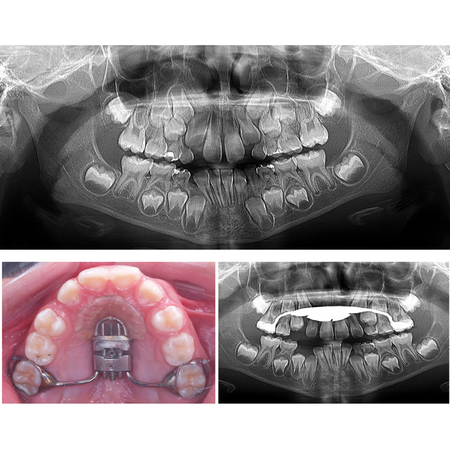

Anteroposterior palatal disjunction and the premaxilla

OBJECTIVE: To biologically substantiate the proposal of anteroposterior palatal disjunction in properly selected cases. METHODOLOGY: The sample from Trevizan’s (2018) master’s dissertation and its inferences were used to support the biological basis of this procedure. RESULTS AND DISCUSSION: Signs of the premaxilla– maxilla suture were observed in all specimens up to 12 years of age, and in 6.16% of the adult skulls analyzed, which supported the proposal of anteroposterior disjunction...